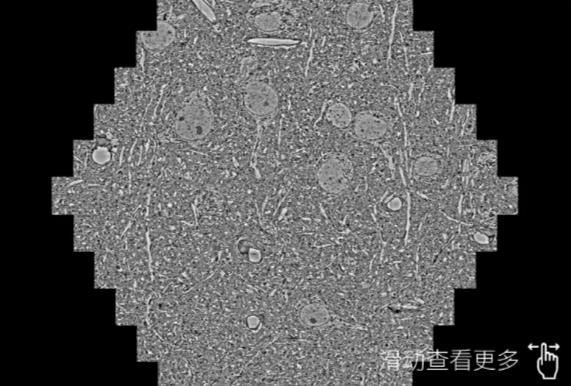

鼠脑切片。左图使用秦皇岛蔡司秦皇岛扫描电镜MultiSEM706对165μmx143pm面积区域成像,耗时仅需1.5秒。右图为鼠脑切片中30μm区域放大效果。样品由芝加哥大学B.Kasthuri提供。

使用蔡司高速秦皇岛扫描电镜MultiSEM对1mm²人脑皮层组织进行高分辨成像,并对其中的各种细胞结构进行三维重构分析。左图展示了2x3mm²组织平面中锥体神经元的三维重构效果。右图显示了局部体积神经元三维重构。图像由哈佛大学chtman实验室提供,渲染图由D. Berger 制作。